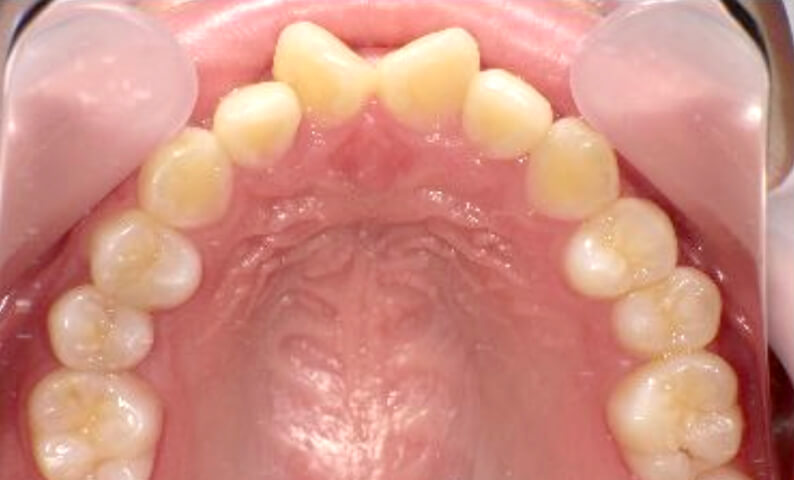

症例_025 上下顎の部分矯正

治療期間:13ヶ月金額:51万円+税女性前歯のガタガタ出っ歯